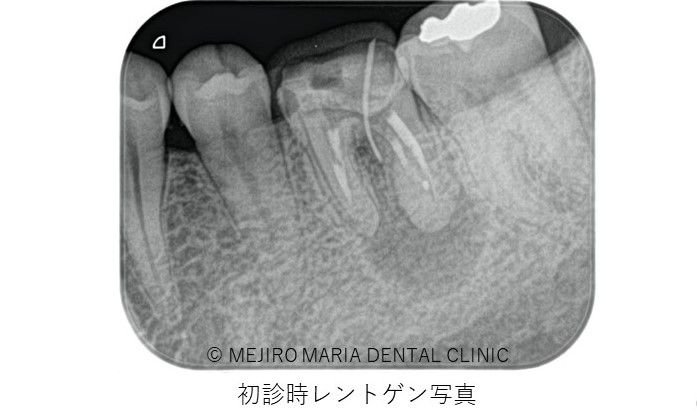

2年以上他院にて根管治療で通院されていた患者様の症例です。長期間通院したにもかかわらず症状は改善されず抜歯の宣告をされ、当院を受診されました。

左下6番直下は大きく腫脹し、サイナストラクト(瘻孔・フィステル)と言われる排膿路が確認できました。